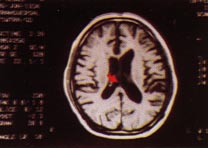

核磁共振檢查診斷

根據上述典型症狀及輔助檢查不難作出診斷。